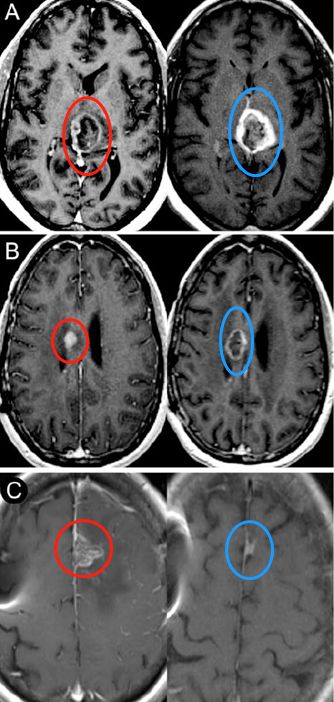

幾項回顧性研究顯示,HGG的全切(GTR)可提高中位生存期,尤其是與單獨(dú)活檢相比。因此,當(dāng)前新診斷HGG的標(biāo)準(zhǔn)治療流程是首選腫瘤全切,然后是替莫唑胺和放射療法。但在某些情況下,患者的身體狀況可能無法耐受開顱手術(shù)切除腫瘤,而且有時腫瘤可能處在雄辯的皮質(zhì)或深層結(jié)構(gòu)的位置,在這種情況下,切除會導(dǎo)致明顯的神經(jīng)功能缺損,對于這些患者,當(dāng)前的治療通常會先行活檢診斷病理,然后進(jìn)行化學(xué)放療,但LITT技術(shù)的廣泛運(yùn)用則為他們提供了新的選擇。在新診斷的HGG中使用LITT的主要治療指征是患有無法手術(shù)的腦腫瘤的患者,如高齡患者或因合并癥而不能進(jìn)行開放手術(shù)的患者。較為適合進(jìn)行LITT前期手術(shù)的常見腫瘤部位包括深灰質(zhì)區(qū)(例如丘腦和基底神經(jīng)節(jié)),胼胝體和島葉(圖4A和B),LITT可以在殺滅腫瘤細(xì)胞的同時將手術(shù)的發(fā)病率降至最低。

圖4:腦腫瘤立體定向LITT激光消融后的影像學(xué)結(jié)果。A:術(shù)前(左)和術(shù)后(右,LITT后3個月)用Gd造影獲得的T1加權(quán)軸向MRI顯示,丘腦GBM是用LITT治療的。術(shù)后圖像顯示治療區(qū)邊緣穩(wěn)定環(huán)形強(qiáng)化。B:術(shù)前(左)和術(shù)后(右,LITT后5個月)用Gd造影獲得的腦軸向T1加權(quán)MRI顯示LITT治療的右側(cè)胼胝體GBM。C:術(shù)前(左)和術(shù)后(右,LITT后3個月)經(jīng)Gd造影獲得的腦軸向T1加權(quán)MRI顯示復(fù)發(fā)額葉GBM的治療。